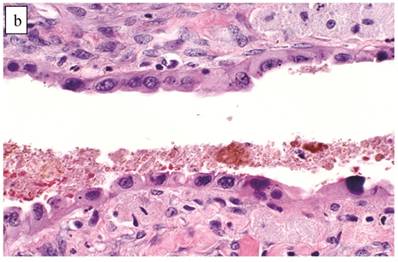

Associations with endometriosis, including comparison with adenofibromatous clear cell CAs, are shown in Tables 2, 3, and 5. The 57 CAs with endometriosis in the ovarian tumor had the following histologic patterns: tubulocystic (n=4), glandular (n=1), solid (n=4), and papillary (n=8). Mixed patterns occurred in 40. Thirty-one of the 46 (67%) cases arising directly within an endometriotic cyst had a predominantly cystic gross appearance. Foci of epithelial atypia in endometriosis in the ovarian tumor were similar to those in endometriosis associated with APTs noted above (Figs. 6 and 7).

Figure 6

Clear cell carcinoma arising within an endometriotic cyst. Typical endometriotic epithelium (bottom) gradually shows greater atypia (middle) as it merges with possible intraepithelial carcinoma (top) and intra-cystic clear cell carcinoma (left).

Figure 7

Atypical endometriotic cyst associated with clear cell carcinoma. (A) The endometriotic cyst contains scattered atypical epithelial cells, which were not directly contiguous with the carcinoma (not shown). (B) The atypical cells have round nuclei and abundant eosinophilic cytoplasm. Some atypical nuclei are hyperchromatic whereas others have irregularly distributed chromatin.